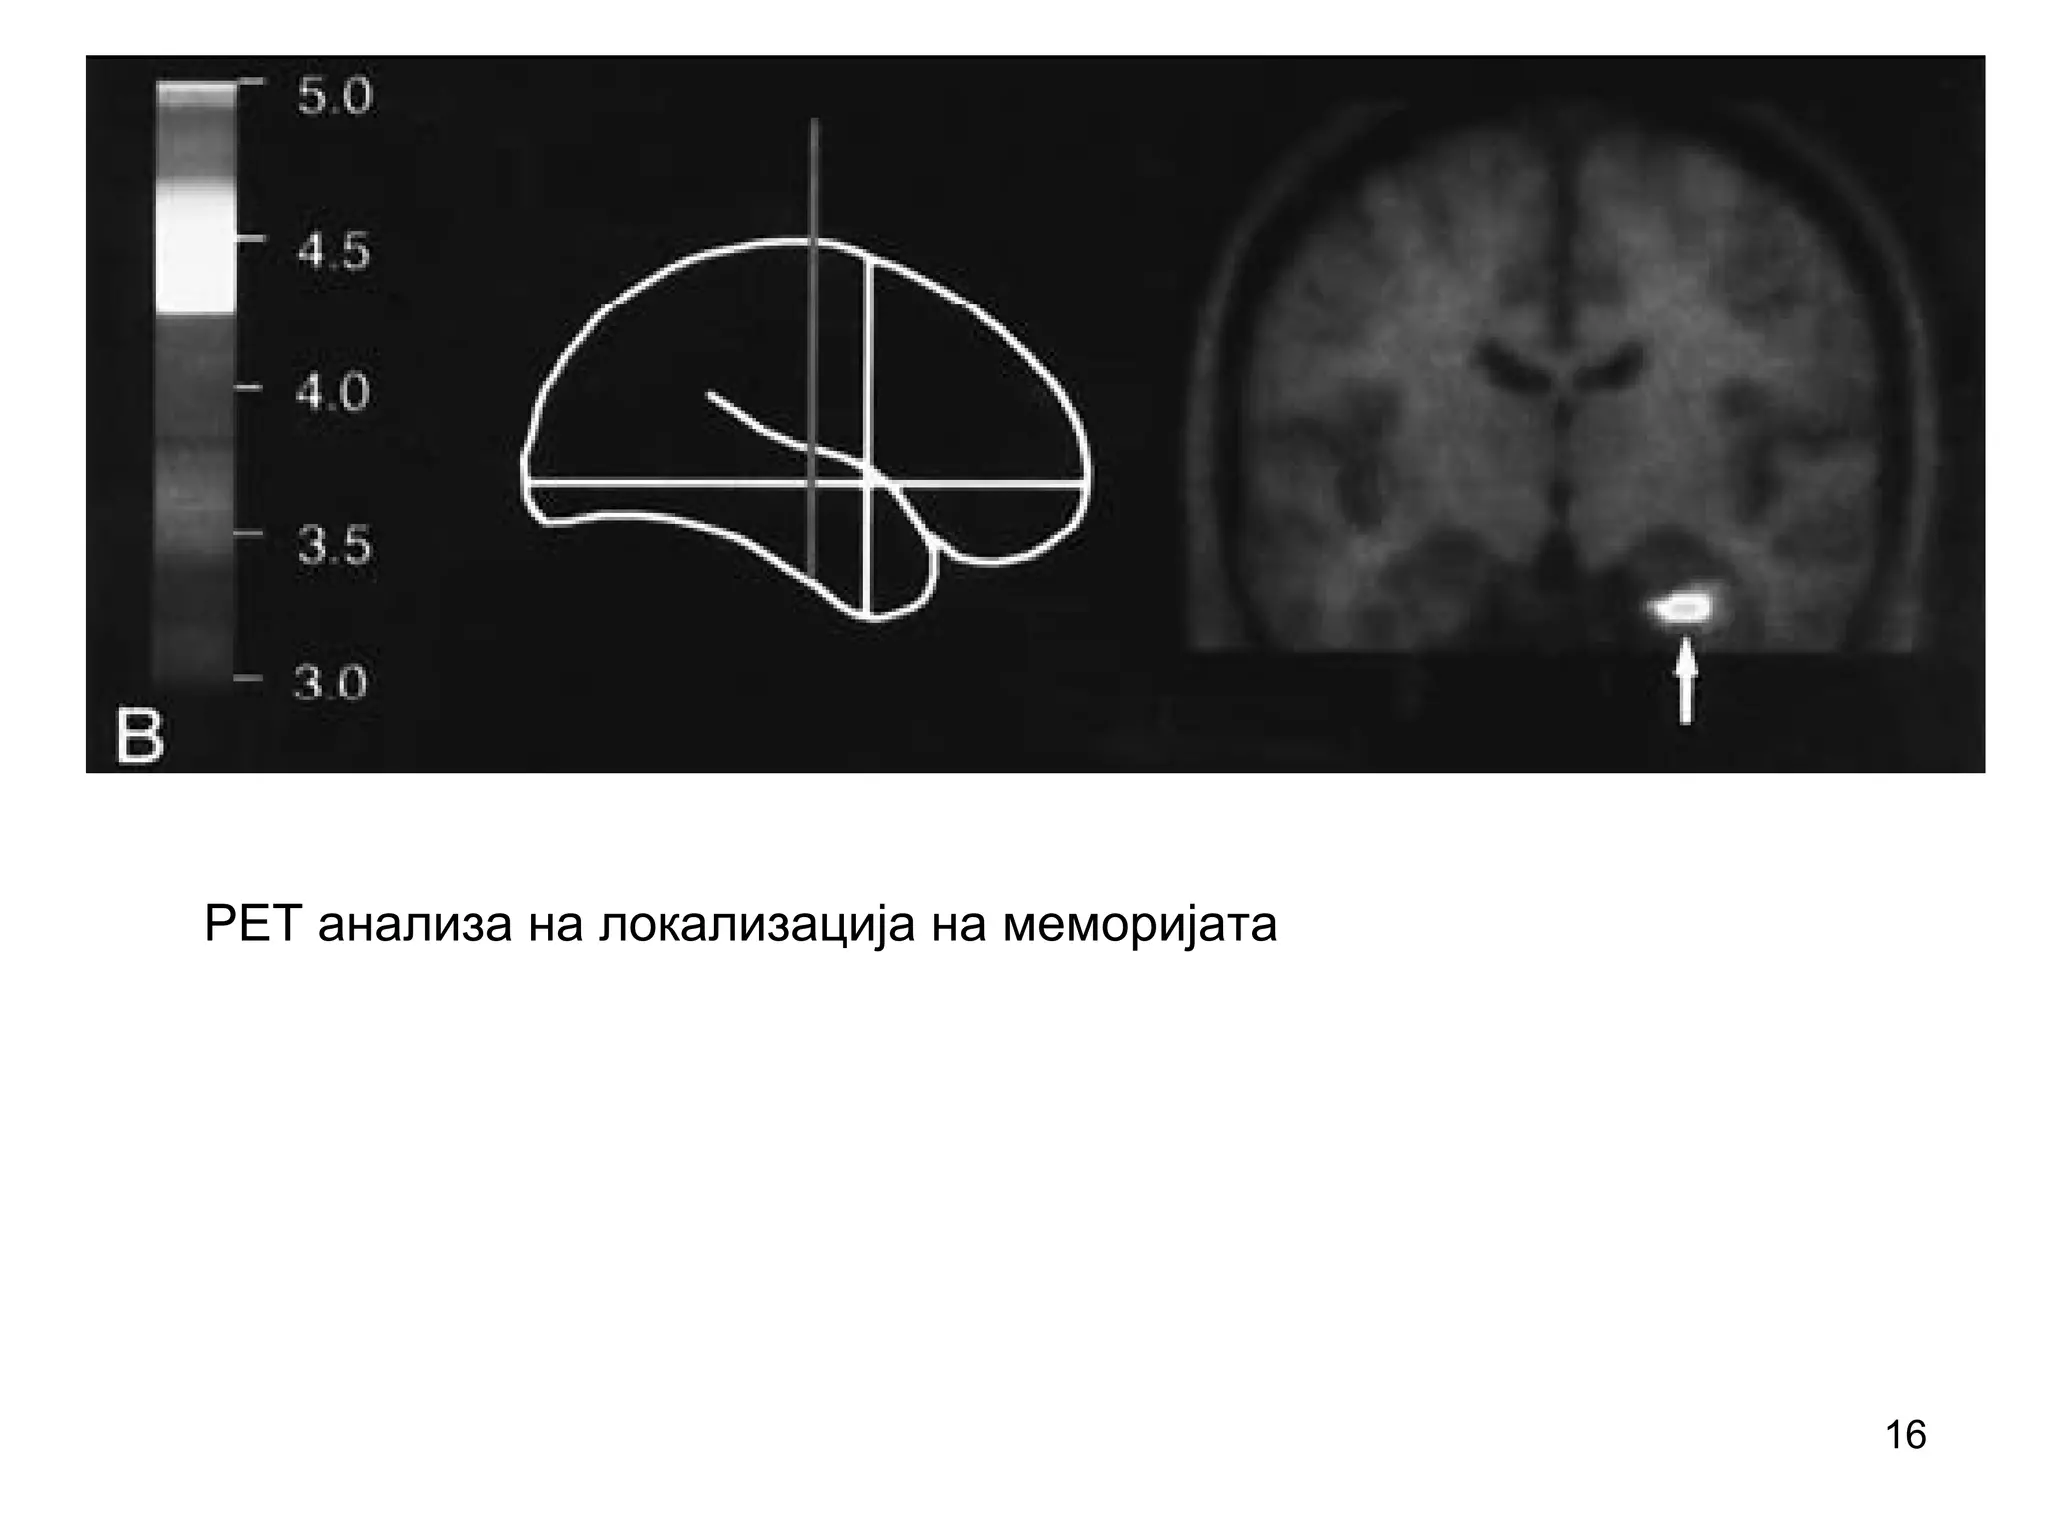

PET анализа на локализација на меморијата

16 PET анализа налокализација на меморијата